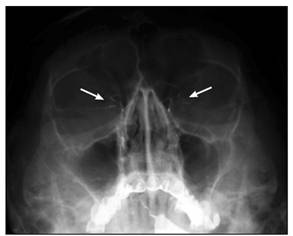

На рентгенограммах глазницы в носоподбородочной,

носолобной и боковой проекциях визуализируются вход в глазницу, ее стенки,

иногда малое и большое крылья клиновидной кости, верхняя глазничная щель (см.

рис. 1).

Рис. 1. Рентгенограммы глазниц в носолобной (а),

носоподбородочной (б) и боковой (в) проекциях

Рис. 4. Дакриоцистограмма. Норма (стрелками

указаны слезные ходы)